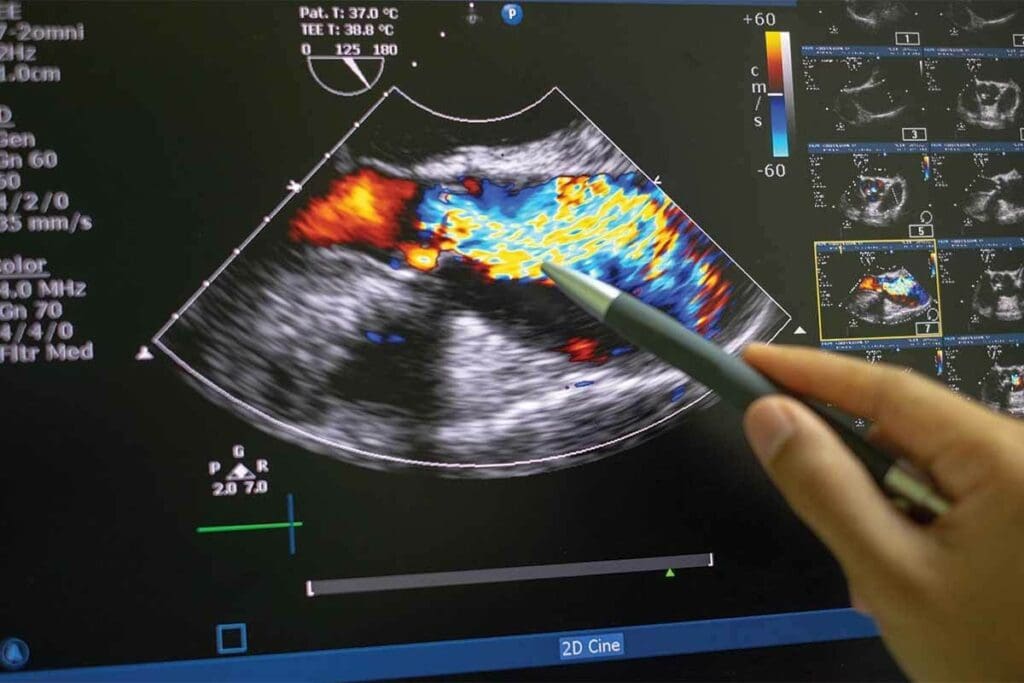

Echocardiograms are key in cardiology, using ultrasound to see the heart’s inside. This method is non-invasive and helps diagnose and track heart issues.

There are many echocardiogram types, each for a different purpose. The most common ones are:

An echocardiogram shows a lot about the heart’s shape and how it works. It can find:

A leading cardiologist says, “Echocardiography is a window to the heart, giving insights for diagnosis and treatment.”

Echocardiography is non-invasive, doesn’t use radiation, and shows images in real-time. But, it depends on the operator and can be hard to see in some cases, like obesity or lung disease.